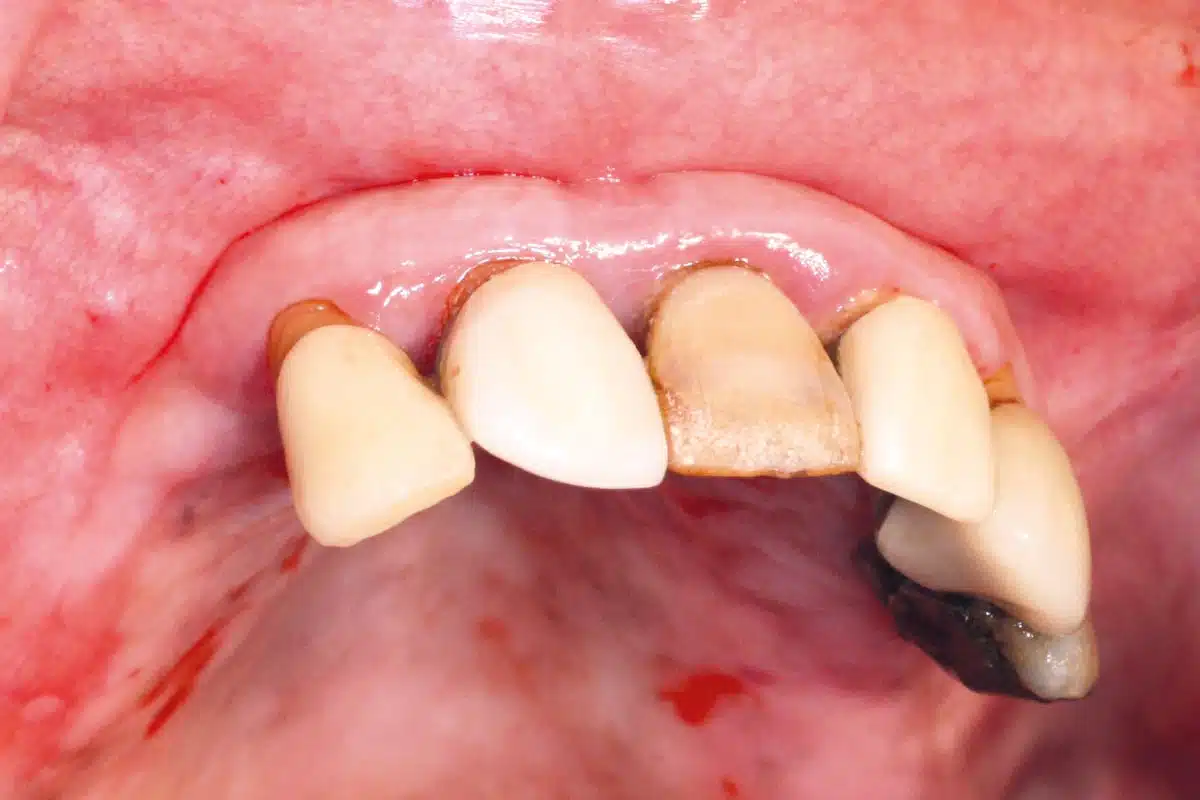

A CBCT scan performed after surgery confirmed accurate implant positioning and successful regeneration of the buccal bone, validating the effectiveness of the regenerative approach. Seven months after surgery, clinical followup demonstrated excellent soft tissue healing. The mucosa was healthy, and abutments were placed with optimal stability, indicating good osseointegration and bone volume preservation.

A definitive prosthetic bridge was placed and trans-screwed onto multi-unit abutments, restoring both function and aesthetics for the patient. A panoramic radiograph taken at 7 months post-op further confirmed the successful outcome, showing stable implant positioning and harmonious integration of the prosthetic solution.